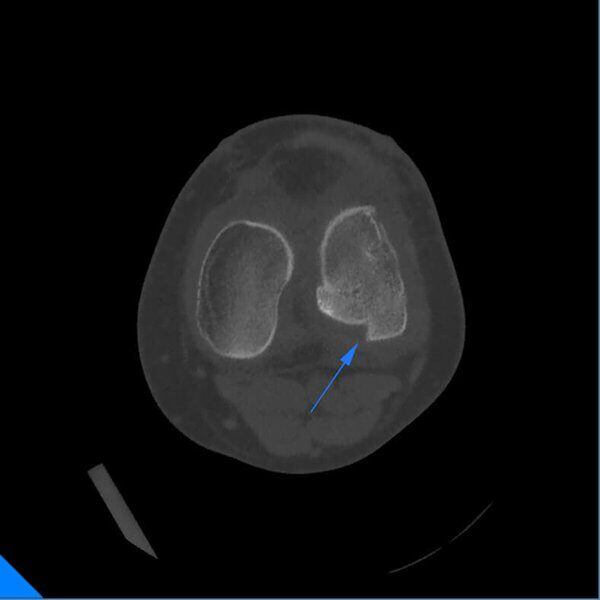

Frattura del Condilo Femorale laterale